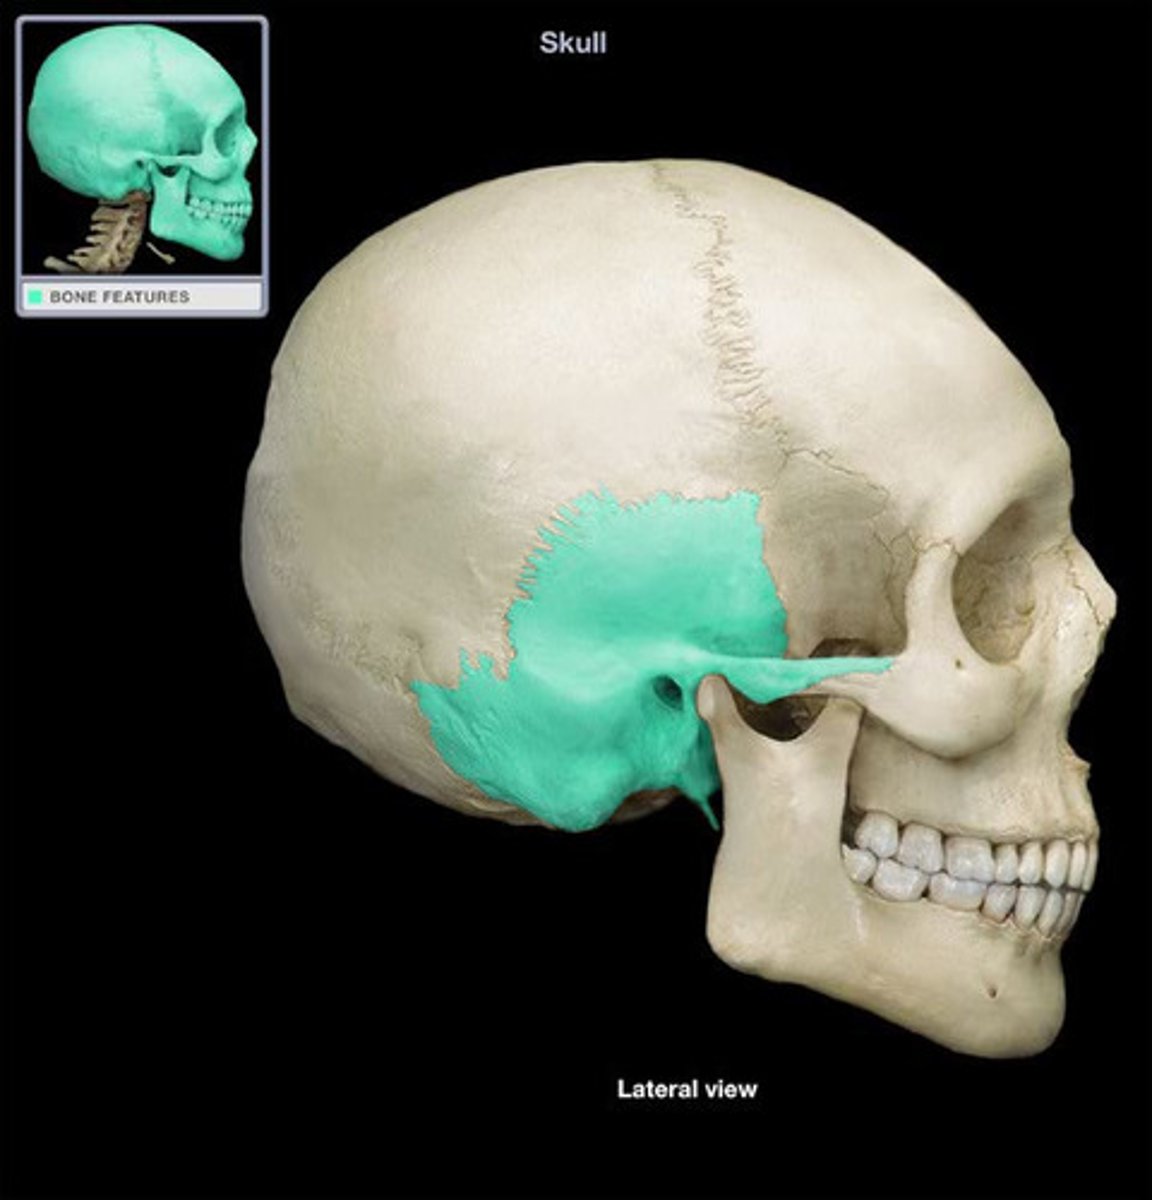

temporal bone

zygomatic process

mastoid process

styloid process of temporal

zygomatic arch